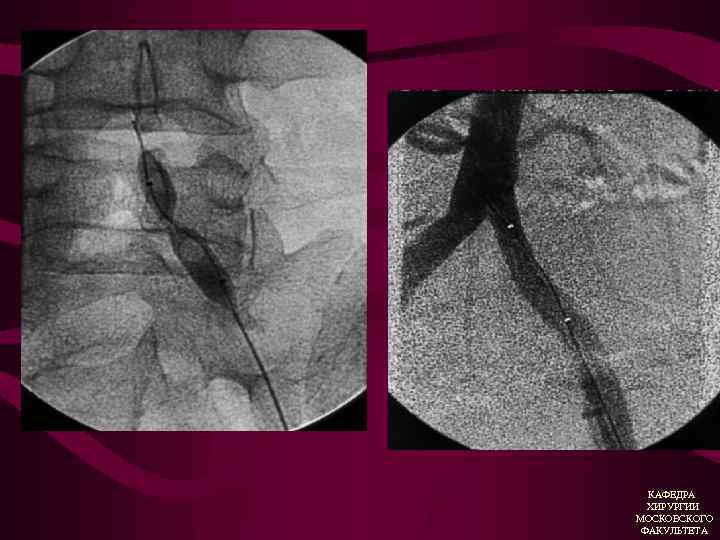

Лечение аневризм брюшной аорты 1. Хирургическое вмешательство (резекция аневризмы с протезированием брюшной аорты) 2. Эндоваскулярное вмешательство (стентирование с установкой стент-графтов) КАФЕДРА ХИРУРГИИ МОСКОВСКОГО ФАКУЛЬТЕТА

Эндоваскулярные вмешательства у больных с ХАН 1. Баллонная ангиопластика 2. Стентирование КАФЕДРА ХИРУРГИИ МОСКОВСКОГО ФАКУЛЬТЕТА